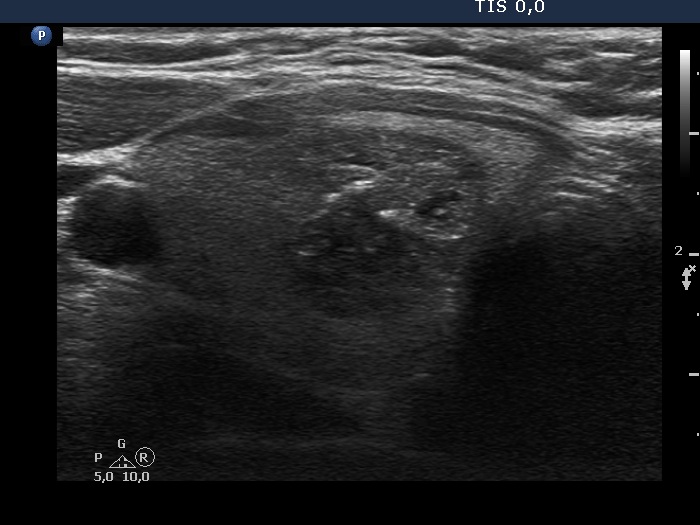

Ultrasonography. The thyroid was echonormal. There was a mass composed of several discrete lesions in the central part of the right lobe.

Comment. This is an equivocal presentation regarding nodule' borders. First, there is a mass composed of distinct nodules which makes the appearance of the borders lobulated. Second, there are some spiculations which are likely within the nodule and not at the borders.